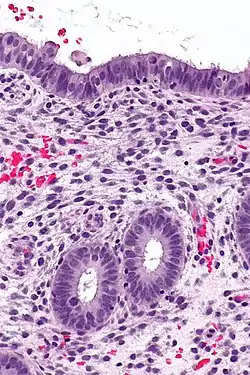

(A) proliferative endometrium (Left: HE × 400) and proliferative endometrial cells (Right: HE × 100)

(B) secretory endometrium (Left: HE × 10) and secretory endometrial cells (Right: HE × 10)